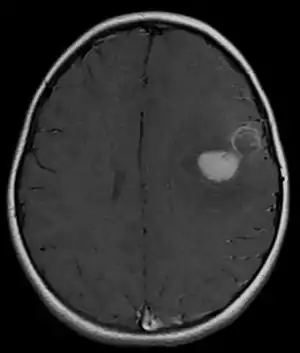

Treatment

The approach to management of a CNS PNET is first to obtain detailed imaging through MRI, as well as additional scans of the patient's body (X-ray, CT, PET, even bone marrow biopsies) to look for metastasis or other associated malignancies. The tumor will then need to be biopsied to confirm the diagnosis. After the diagnosis of a CNS PNET is confirmed, management includes neoadjuvant chemotherapy and radiation (to reduce tumor size burden), complete surgical resection with confirmed negative margins, and/or additional adjuvant post-surgical chemotherapy. CNS PNET is aggressive and must be managed as so. Palliative care services should also become involved in the patient's care team when the diagnosis is made. [6]